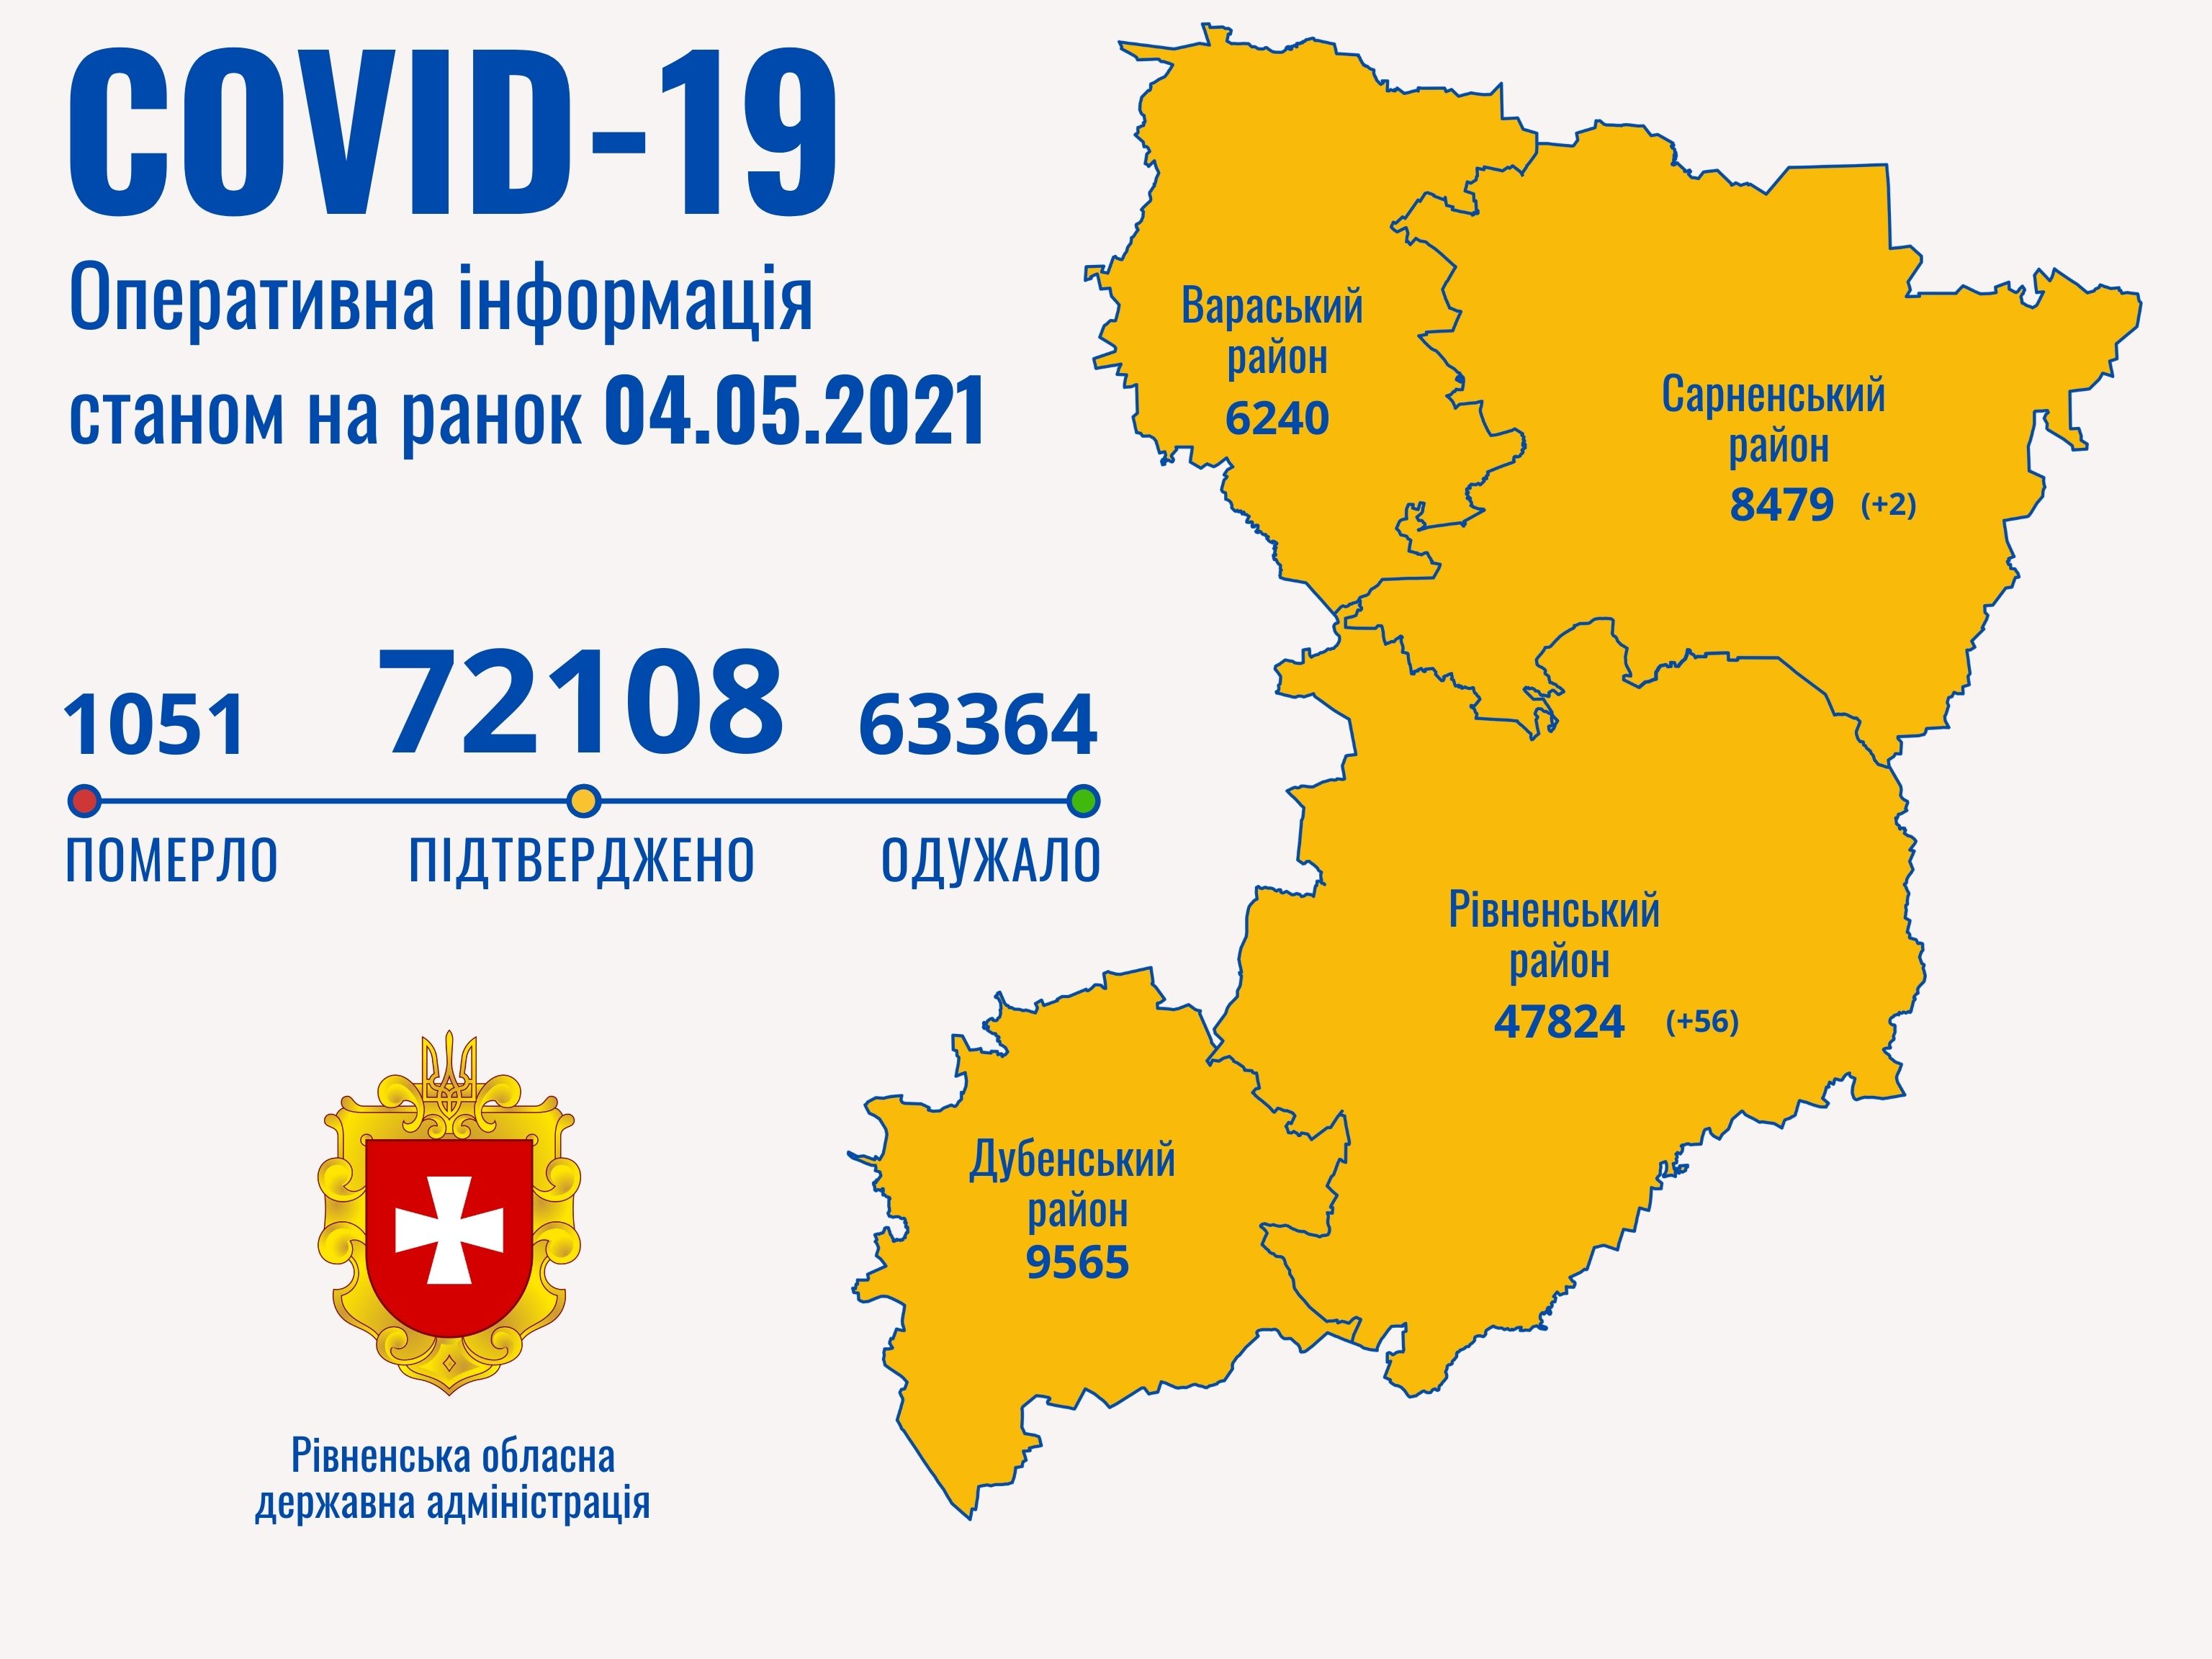

Пів тисячі - у важкому стані, 9 жителів Рівненщини померли за добу від коронавірусу

12.04.2021 10:17